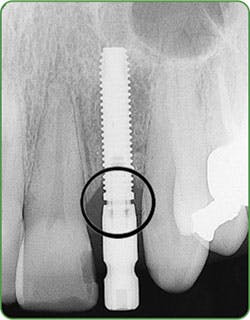

Figures 3a-b: Threads clearly in focus and CBCT (courtesy of Jeff Carlson, CDT, and Dr. R. Horowitz).

For one to four implants, take a vertical bitewing or periapical film. For five or more implants, take individual periapical radiographs, panoramic film, or a three-dimensional radiograph (cone beam computed tomography-CBCT scan). Line up the diagnostic radiograph of the implant correctly, with all indentations of the implant and the threads clearly in focus4,8 (Figure 3a-b).